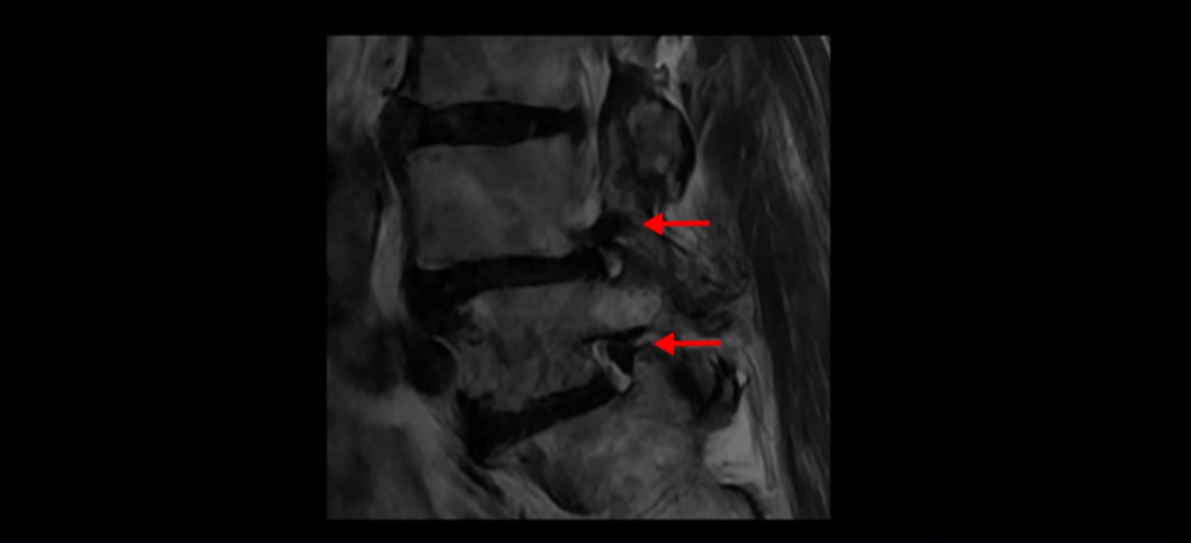

제가 먼저 이분 MRI를 보고 설명해 드린 후 어떻게 이런 분들을 수술 없이 허리 기능재활치료로 호전시킬 수 있는지 자세히 설명드리겠습니다. 이분 허리가 보시다시피 여러 마디가 퇴행되어 있고

4번 5번에는 뼈가 밀려 나간 전방전위증도 있습니다.

X-ray로 보면 뼈가 밀려 나간 게 더 잘 보입니다.

4번 5번 마디를 자세히 보면 심한 중심성 협착이 있어서 신경 구멍이 매우 좁아져 있습니다.

또 신경 가지가 빠져나가는 추간공도 매우 좁아져 있습니다.